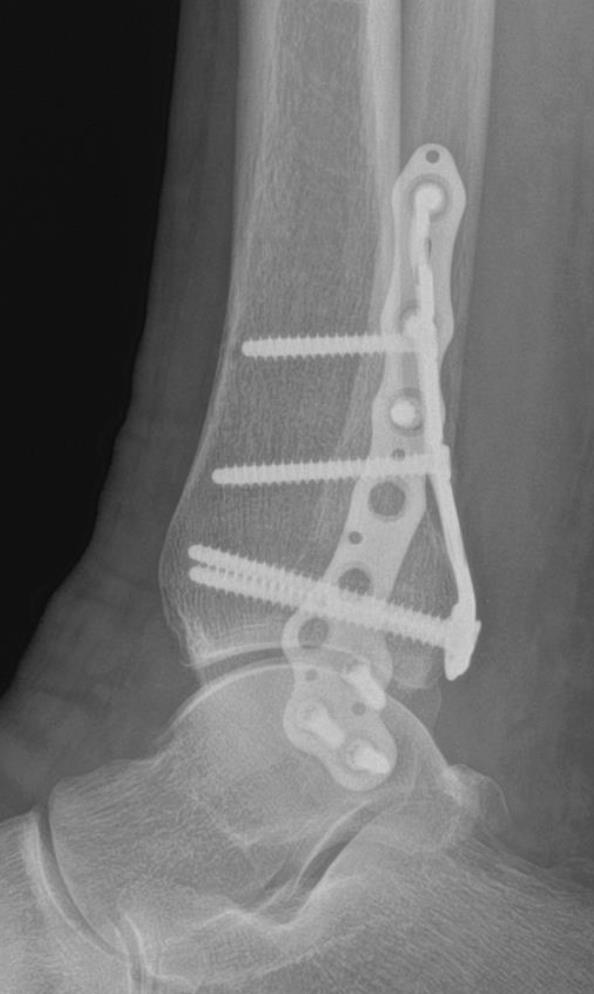

Volition® Ankle Fracture Plating

• VolitionTM Ankle Fracture Plates are available in six varieties: anatomic fibula plate, straight fibula plate, anatomic medial malleolar plate, posteromedial tibial plates (Type IIB), posterolateral tibial plates (Type IIA) and posterior tibial plates (Type III).

• posterolateral approach advised for type iia fractures

• medial-posteromedial approach advised for type iib fractures

• posteromedial approach advised for type iii fractures

• lateral anatomical fibular plate

• posterolateral tibial plates (type iia)

• posteromedial tibial plates (type iib)